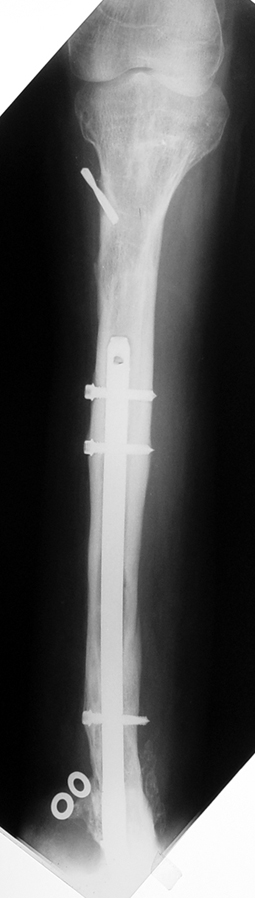

3. POSTTRAUMATIC LOWER LIMB SHORTNESS (MALUNION)

This type of shortness occurs after a fracture heals in a shortened position. Most cases are seen in adults and can be treated with one lengthening operation. Additional deformities can be corrected simultaneously. Most of these cases can be treated with lengthening over nail or just corrections and intramedullary nailing.